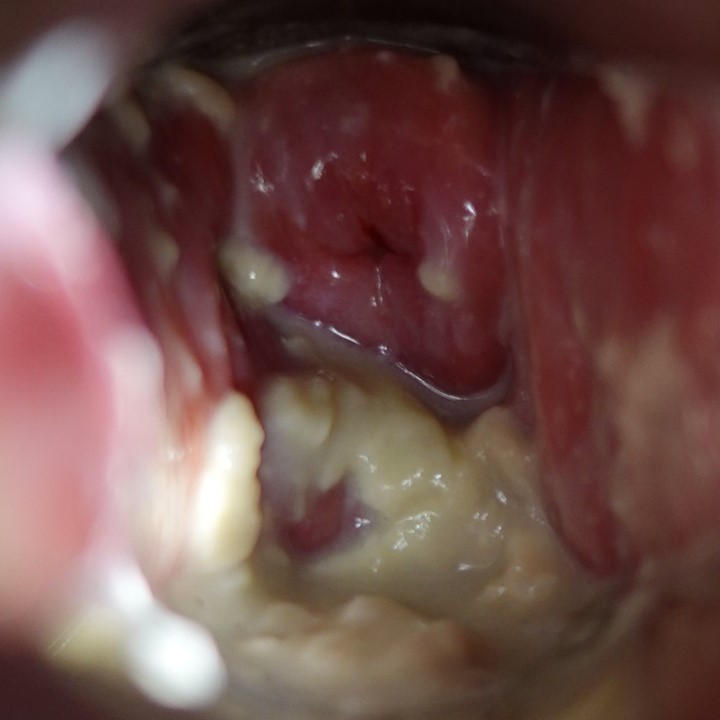

診察では、クリトリス周囲、両側大陰唇・小陰唇、会陰、膣前庭部、尿道周囲に無数のコンジローマ結節を認めました。(Before, 画像1)

さらに会陰部や大陰唇には亀裂が多数みられ、皮膚炎と感染の併発が疑われました。(画像2)